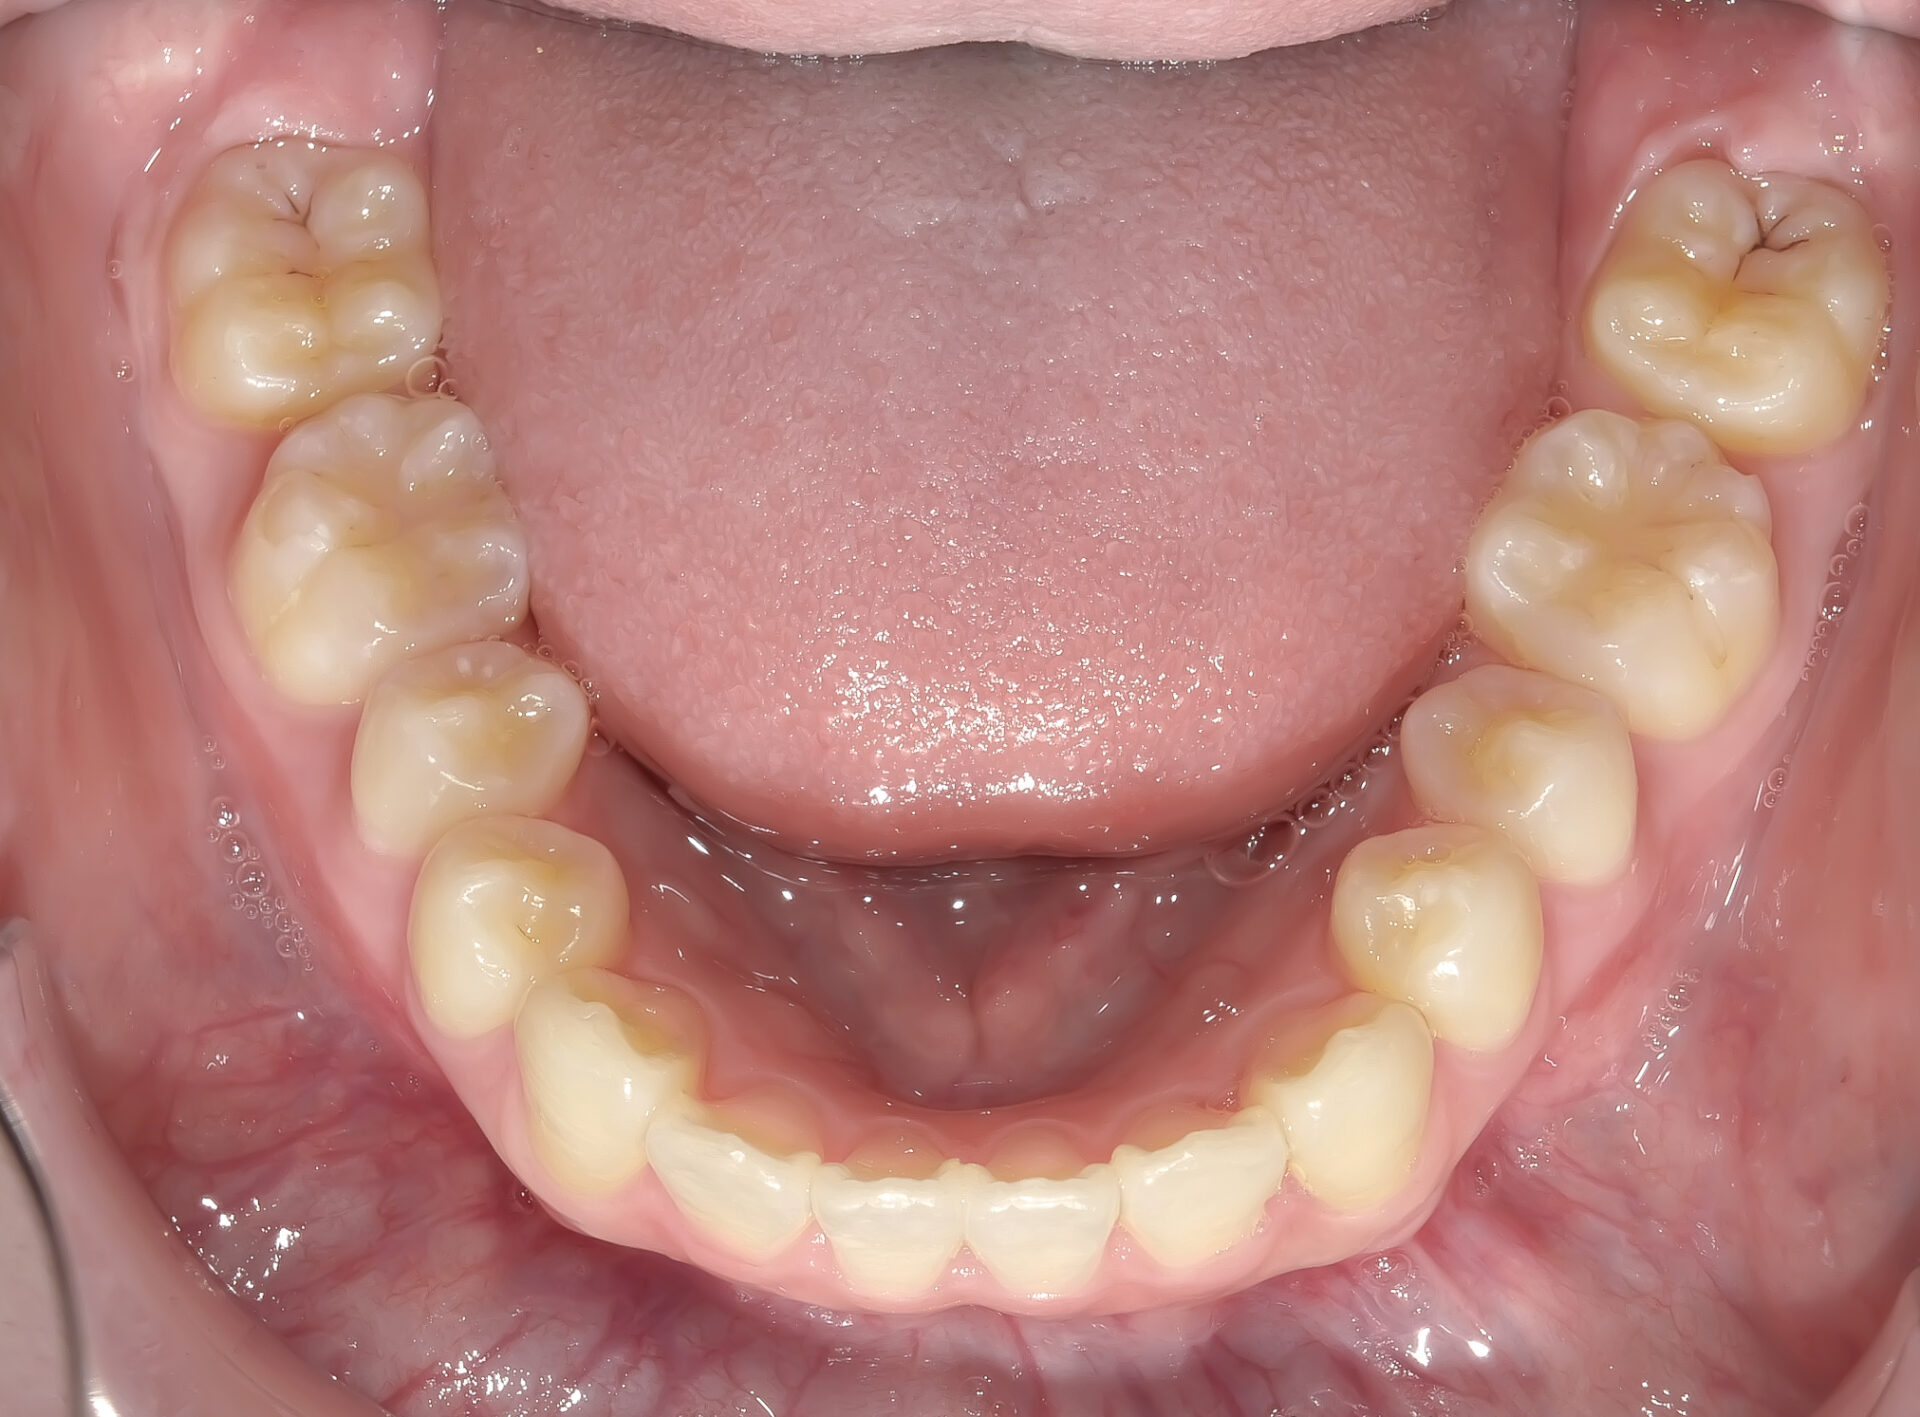

下顎の前歯に叢生(ガタガタ)を認めます。

治療終了時の写真です。

ほぼすべての歯が歯列弓上にきれいに並んでいます。

上下ともしっかり並びました。